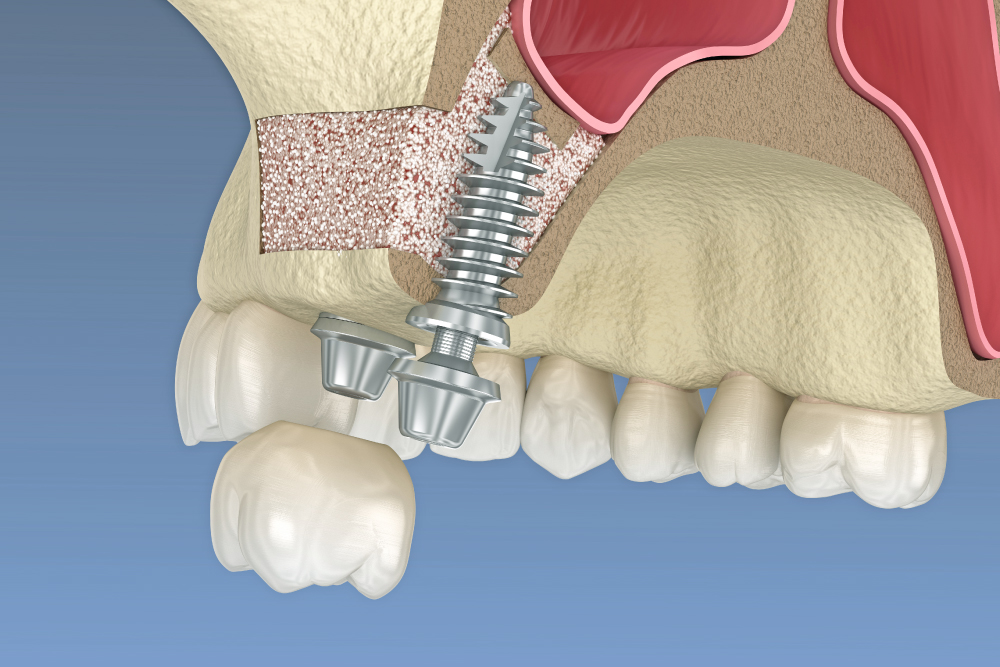

インプラントは、歯を失った部分の顎の骨に「チタン製の人工歯根」を埋め込み、その上に人工歯(セラミックの歯)を装着して歯の機能を回復する治療です。

・顎の骨の量・形・神経の位置を3Dで確認

・術中のリスクを最小限に

・適切な埋入角度・深さを事前にシミュレーション

骨が不足しているとインプラントが難しいケースがありますが、当院では以下のような補助手術にも対応可能です。

・GBR法(骨再生治療)

・ソケットリフト

・サイナスリフト